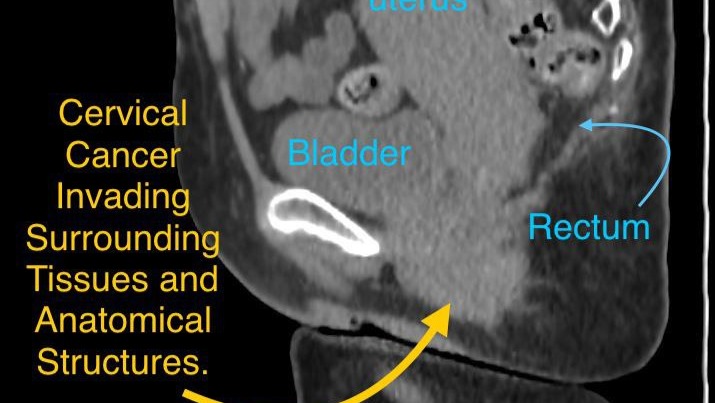

Our mom is only 51 years old, but right now, she’s fighting for her life. She has been diagnosed with advanced cervical cancer that has already spread beyond her uterus into her bladder, rectum, and even her lungs. Every single day has been a battle against pain, fear, and uncertainty and yet she keeps smiling, trying to protect us from her suffering.

The current objective is to shrink the tumor enough to make surgery possible. But this is not a simple operation. It’s a complex, high-risk procedure that will involve removing her entire uterus, rectum, and possibly her bladder. It may even require two separate surgeries to ensure safety and success. The cost for this life-saving surgery in a reputable hospital Mexico is about $15,000 USD. We’ve done everything we can borrowed money, sold personal belongings, and taken side jobs but no matter how hard we try, we simply can’t afford it on our own. We’re two young adults trying to save the woman who raised us, who taught us kindness, and who always believed that even in darkness, there’s light.

Dr. Arguello believes this surgery is the only realistic way to save her life; the treatment cannot overcome that amount of cancer. The surgery would reduce the tumor burden by 90% in a matter of hours.